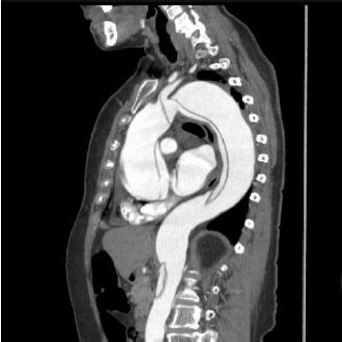

Observe a imagem.

Das condições a seguir, assinale a que não está geralmente associada à emergência cardiovascular visualizada na imagem.

Paciente no pós-operatório de cirurgia de troca de válvula aórtica eletiva, função ventricular com leve disfunção ventricular esquerda. Foi admitido na unidade de pós operatória em boas condições. Aproximadamente cinco horas após sua admissão, apresentou pressão arterial de 80 mmHg X 40 mmHg, pressão venosa central de 20 mmHg, frequência cardíaca de 120 bpm e em ritmo sinusal, a diurese de 20mL na última hora. Dreno de mediastino tubular 34, apresentou 100mL nas últimas três horas.

Nesse caso, o diagnóstico mais provável do problema é: